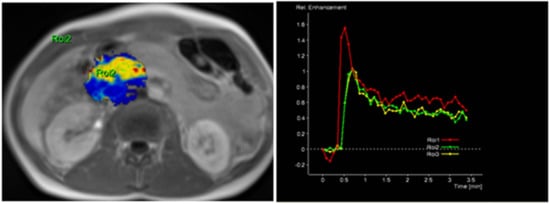

The radiological findings were compared with histopathological data. Histopathological analysis was performed at the Department of Pathological Anatomy, Lithuanian University of Health Sciences. The study patients were further grouped according to the differentiation grade (G value): well- and moderately differentiated (G1 + G2) and poorly differentiated (G3) PDAC. Images of DCE-MRI of non-tumorous pancreatic tissue and PDAC are presented in Figure 2 and Figure 3.

Figure 2. MRI perfusion images of non-tumorous pancreatic parenchymal tissue in the head of the pancreas with TSIC—Type I (characterized by fast enhancement and fast washout). Type I pattern enhancement was found in all tissues from control group patients.